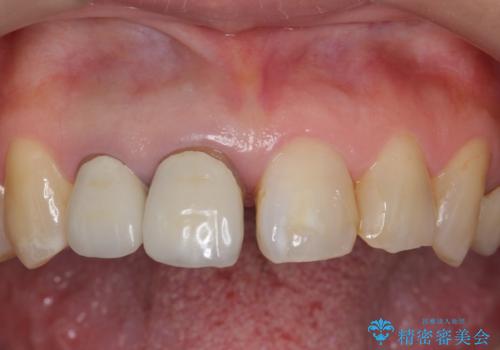

右上の前歯二本、左上の前歯1本をセラミックにし、正中の前歯を2本連結しました。

連結しなくても、ナイトガード使用で防止できると説明しましたが、手間をかけずに二度と広がらない方がいいとのことで連結を強くご希望でした。

気になっていたすき間が閉じて、大変喜んでいただけました。